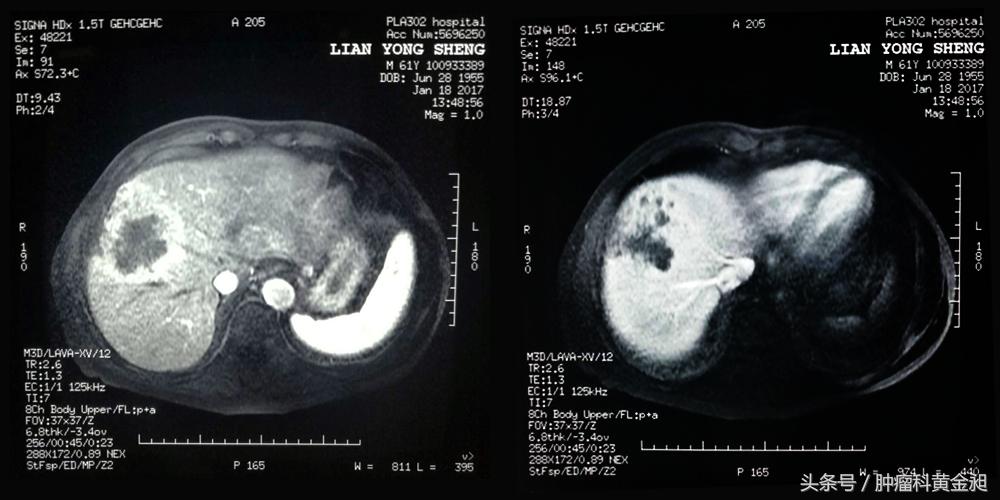

2016年12月确诊肝癌,于某三甲医院行介入栓塞治疗后并未好转,术后一月复查肿瘤无坏死、继续增大,肿瘤由治疗前的4.8*3.8cm和1.0*0.6cm增大到7.2*5.6cm和1.5*0.9cm,且栓塞后综合征反应强烈,患者非常痛苦。

2017年1月22日,就诊于我科室,此时复查肿瘤已增大到9.4*5.9cm,于2017年1月25日由我科室副主任李睿行介入化疗栓塞治疗,术后肿瘤的供血血管被堵塞,肿瘤血管染色消失,术后24小时,肿瘤开始坏死,患者出现高热,39.0℃,但患者无寒颤,为典型的吸收热表现。查体示患者脉弦,故李大夫采取耳尖放血以泻热祛邪,后背膀胱经走罐以疏通经络,支沟穴、阳陵泉下3寸针刺以理气,并配合火针围剿抑瘤等中医特色疗法,金匮统元方加减以改善食欲,健运脾胃。患者术后体力恢复迅速,栓塞后综合征的各种反应很快就消失了。两周后复查CT,显示肿瘤坏死,缩小。

术前影像

患者术后恢复迅速,复查肿瘤区域坏死,缩小